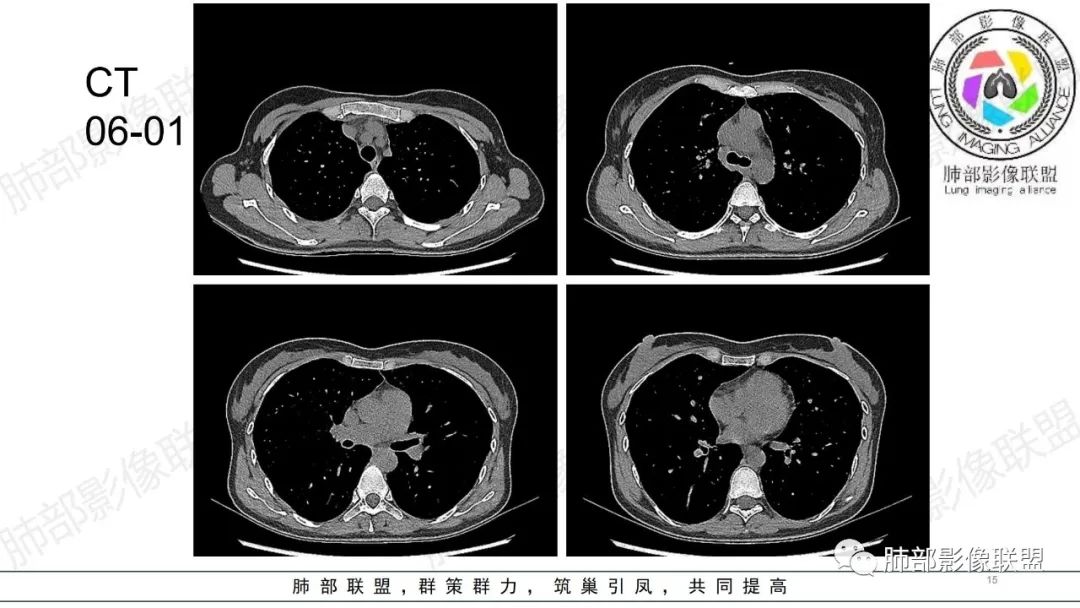

34岁女性患者,“哮喘”病史30年,近期有可疑刺激性气体吸入史;因乏力半年,咳嗽、憋气、发热4天就诊;6.1CT提示双肺广泛毛玻璃影及粟粒样结节,胸膜下闲置及血管周闲置,可见树丫征,部分小叶间隔增厚。考虑:1.过敏性肺泡炎,有可疑刺激气体接触史,胸膜下闲置,广泛毛玻璃影,地图样分布,粟粒结节边界模糊,支持过敏性肺泡炎,但糖皮激素治疗效果不佳,且动态复查血常规血红蛋白进行性降低,过敏性肺泡炎 不符合;2.肺含铁血黄素沉积症:患者30“哮喘”病史,可能为肺含铁症状,肺部CT提示双肺弥漫毛玻璃影及粟粒结节影,中下肺明显,肺底部分小叶间隔增厚,近期咳嗽、憋气、发热,血常规血红蛋白进行性下降,考虑肺含铁急性期症状,但临床无咯血症状,肺含铁不典型。综合考虑:肺含铁血黄素沉积症>过敏性肺泡炎。

年轻女性 ,急性喘息发热,肺部影像弥漫磨玻璃密度,部分细小腺泡结节,胸膜下黑线显示,短期复查,病变密度增高,下肺明显,血管周围肺组织累及较少、且逐渐成小叶间隔分布。考虑弥漫肺泡内病变,并经淋巴道转移,下肺比上肺明显,多为免疫细胞功能下肺较强。1.过敏性肺泡炎,有相关病史,三层密度特点、头尾测分布,符合。2 肺泡微石症,多有钙化,且缓慢起病,病程不太符合,放待排。3 吸入相关肺损伤,有病史,疾病演变过程也符合渗出-肉芽肿改变,建议详细询问病史。4 感染性病变,结核?病变气道分布为主,如此弥漫且没有树丫不符合。5.巨细胞病毒,可以磨玻璃 结节 改变,没有免疫缺陷病史。最后考虑吸入所致 1过敏性肺泡炎、吸入性肺损伤 鉴别肺泡微石症。

年轻女性,两肺多发磨玻璃影,沿气道至肺泡分布,考虑过敏性肺泡炎可能性大。